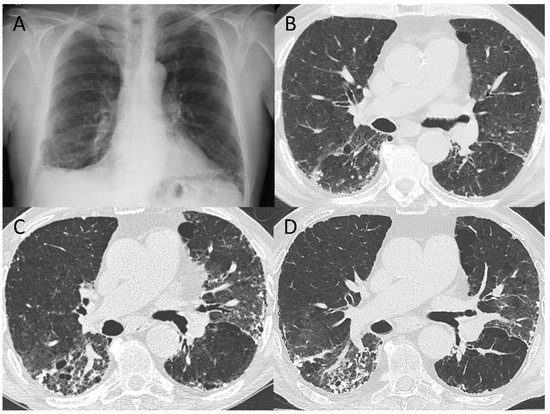

3.2. 5–7-Month Follow-Up CT Scan

3.4. Pattern Evolution